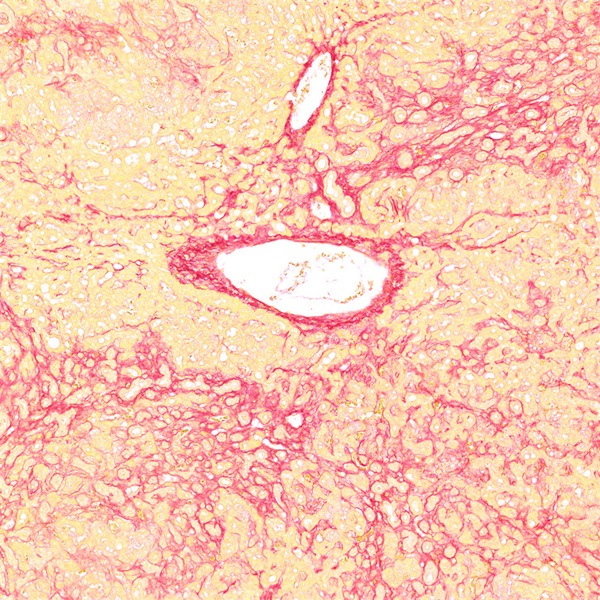

天狼猩红染色

天狼猩红和KWS都是强酸性染料,易与胶原分子中的碱性基团结合,吸附牢固。偏振光镜检查,胶原纤维有正的单轴双折射光的属性,与KWS-天狼猩红结合,可增强双折射,提高分辨率,从而区分两型胶原纤维。未脱钙骨组织切片经天狼猩红染色后,普通光学显微镜下,胶原纤维呈红色或鲜红色,其他呈黄色;在偏振光显微镜下,Ⅰ型胶原纤维呈强橙黄色或亮红色,Ⅲ型胶原纤维呈绿色。

<天狼星红-肝>